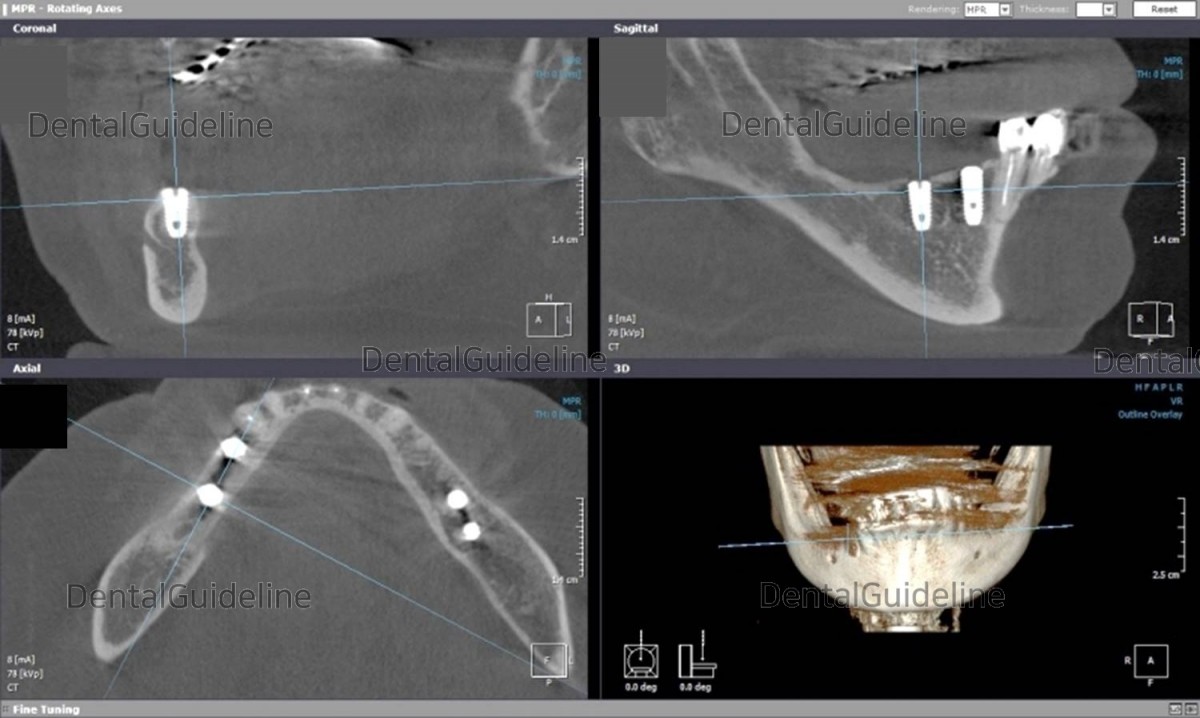

CBCT

after 1 month of implant surgery.![]()

CBCT after 1 month of implant

surgery. The lateral alveolar bone of the implant is thin.